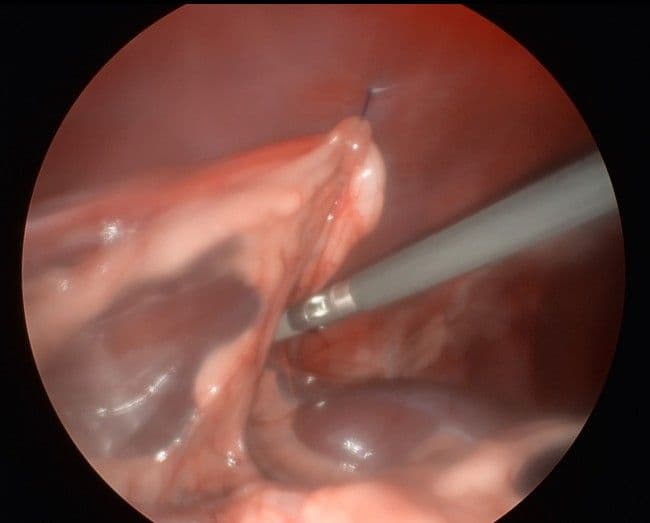

실제 수술 및 시술 사례

최소 침습으로 진행되는 복강경 수술의 실제 모습입니다.

소장 생검 시야

정밀 수술 시야